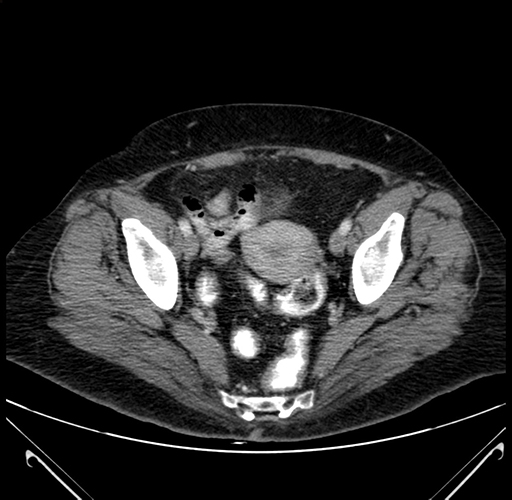

Pre-Chemo: Coronal Venous

Coronal Venous